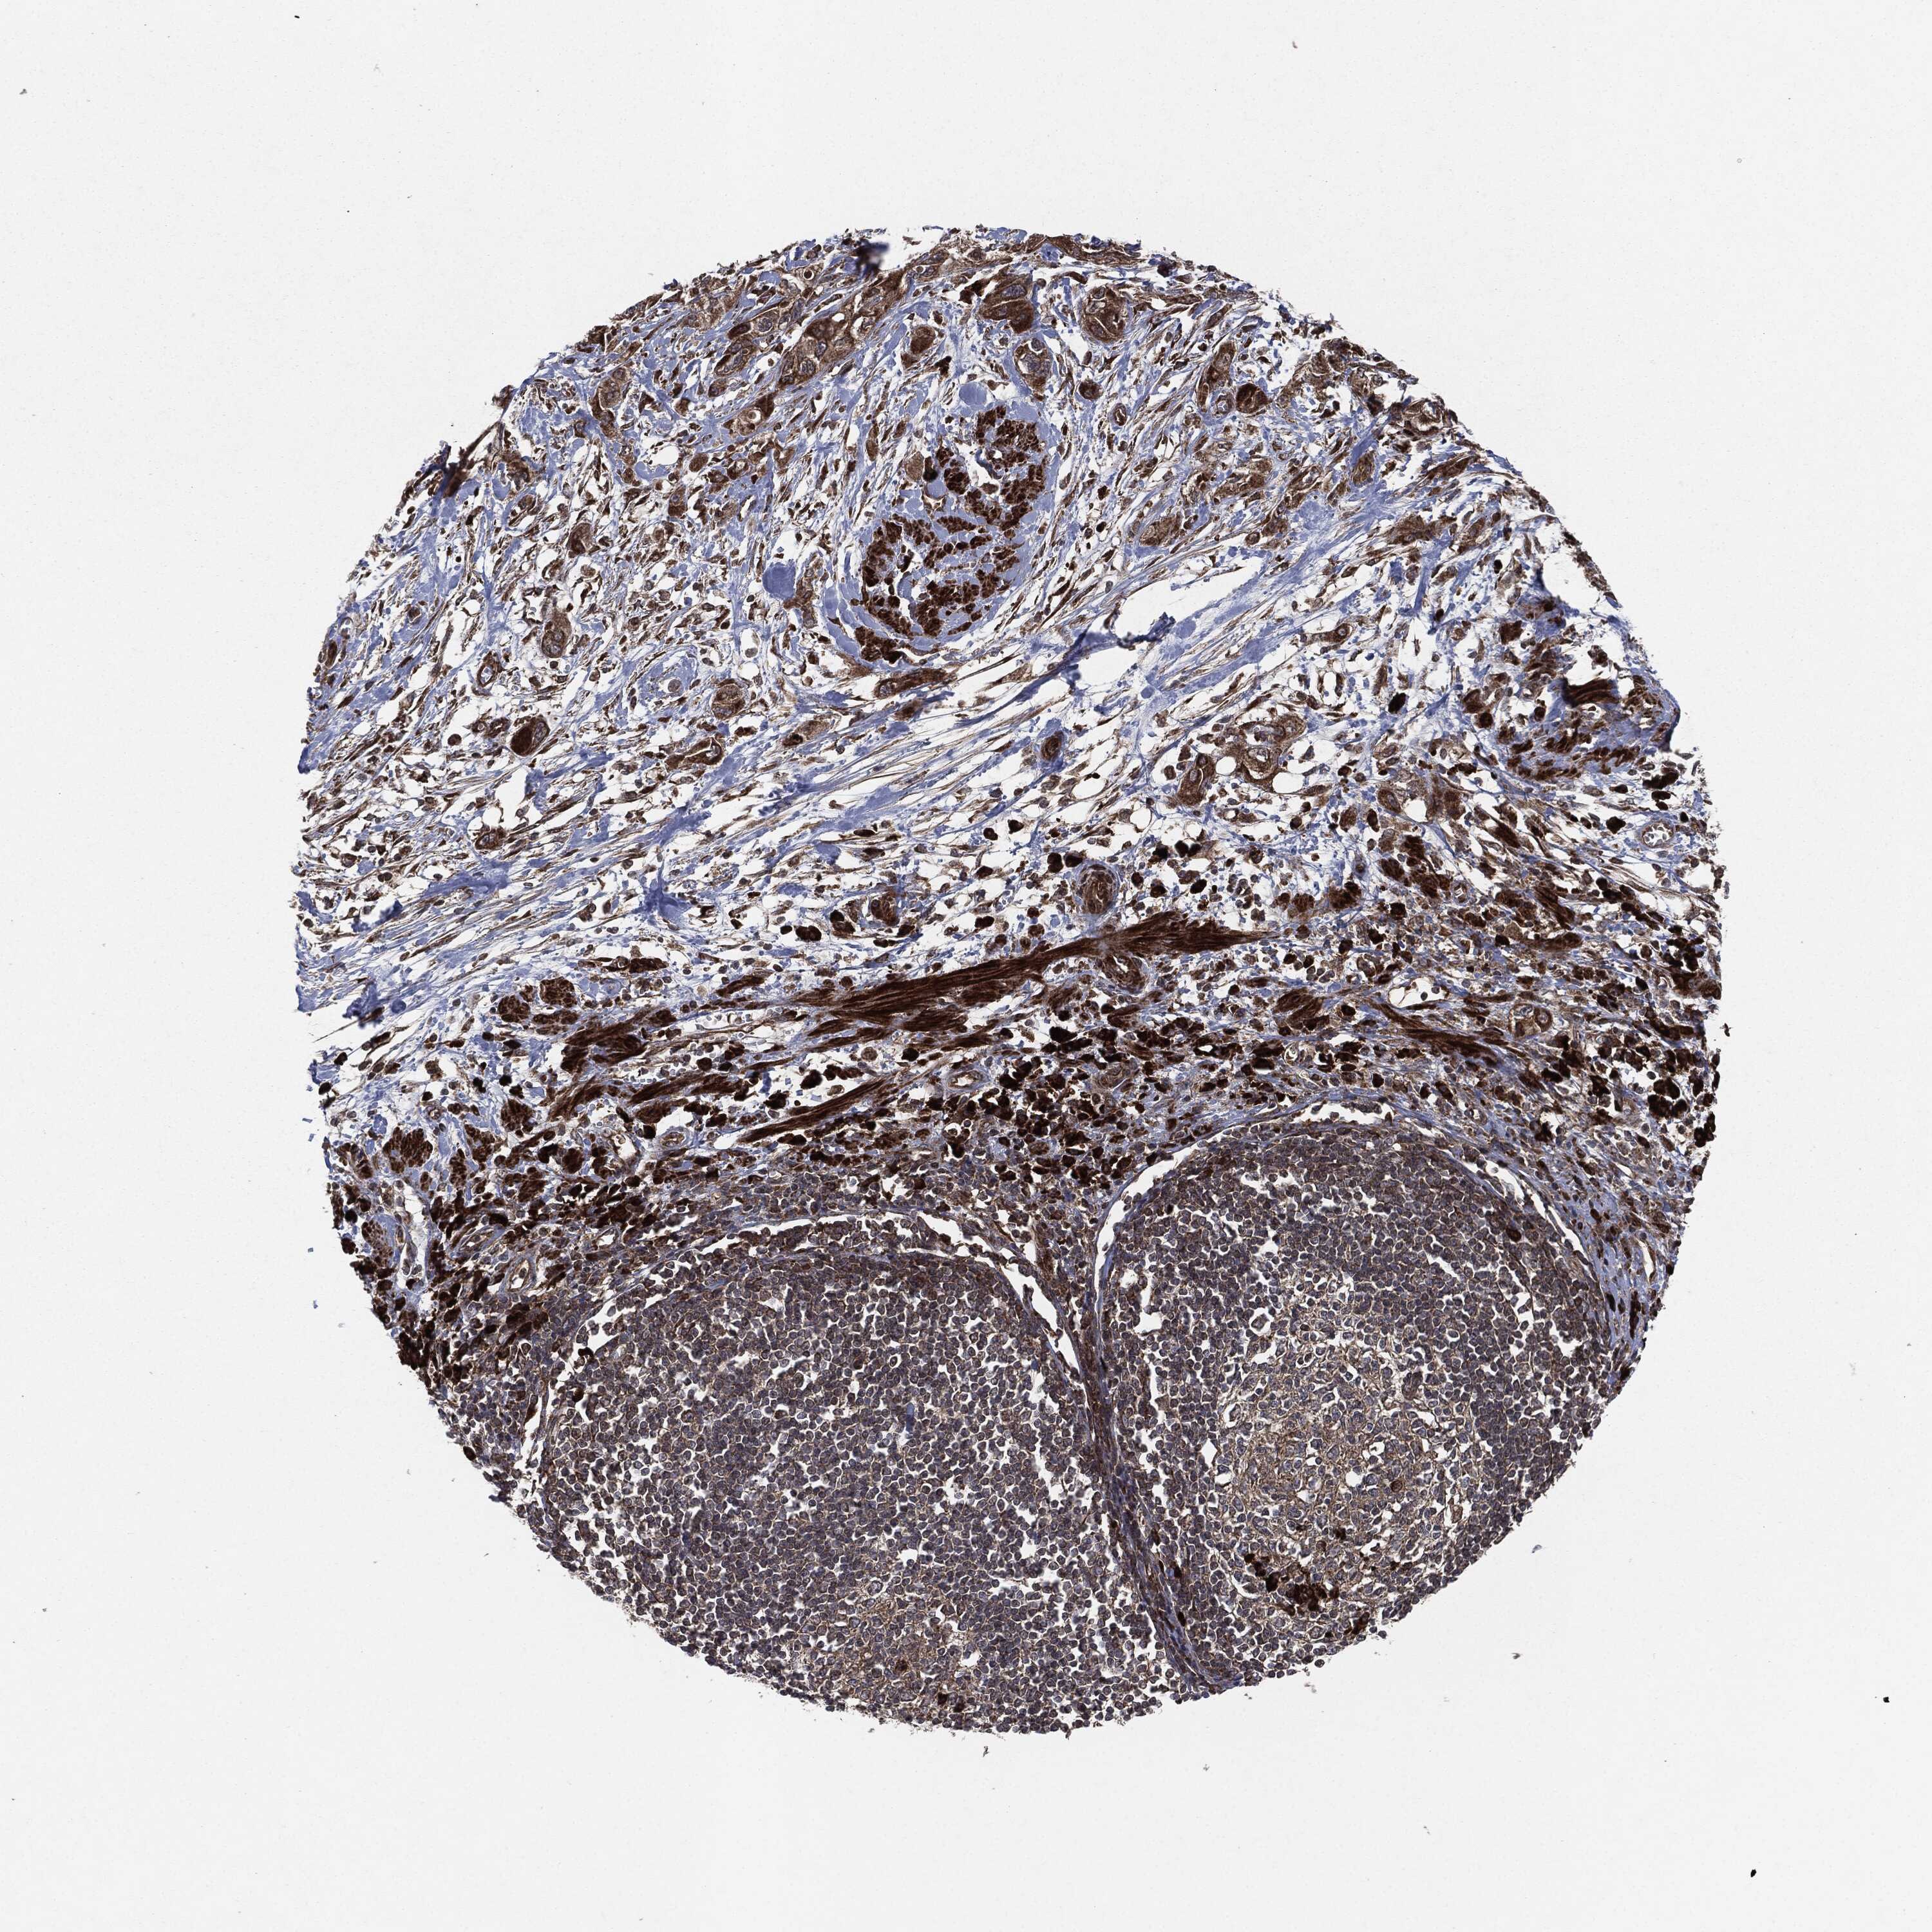

PANCREATIC CANCER - Protein expressioni

A mouse-over function shows sample information and annotation data. Click on an image to view it in a full screen mode. Samples can be filtered based on level of antibody staining by selecting one or several of the following categories: high, medium, low and not detected. The assay and annotation is described here.

Note that samples used for immunohistochemistry by the Human Protein Atlas do not correspond to samples in the TCGA dataset.

Antibody stainingi

Antibody staining in the annotated cell types in the current human tissue is reported as not detected, low, medium, or high, based on conventional immunohistochemistry profiling in selected tissues. This score is based on the combination of the staining intensity and fraction of stained cells.

Each image is clickable and will lead to virtual microscopy that enables deeper exploration of all samples and also displays staining intensity scores, fraction scores and subcellular localization as well as patient and tissue information for each sample.

Antibody HPA002640

Antibody CAB019291

Antibody CAB080384

Adenocarcinoma, NOS

Adenocarcinoma, metastatic, NOS